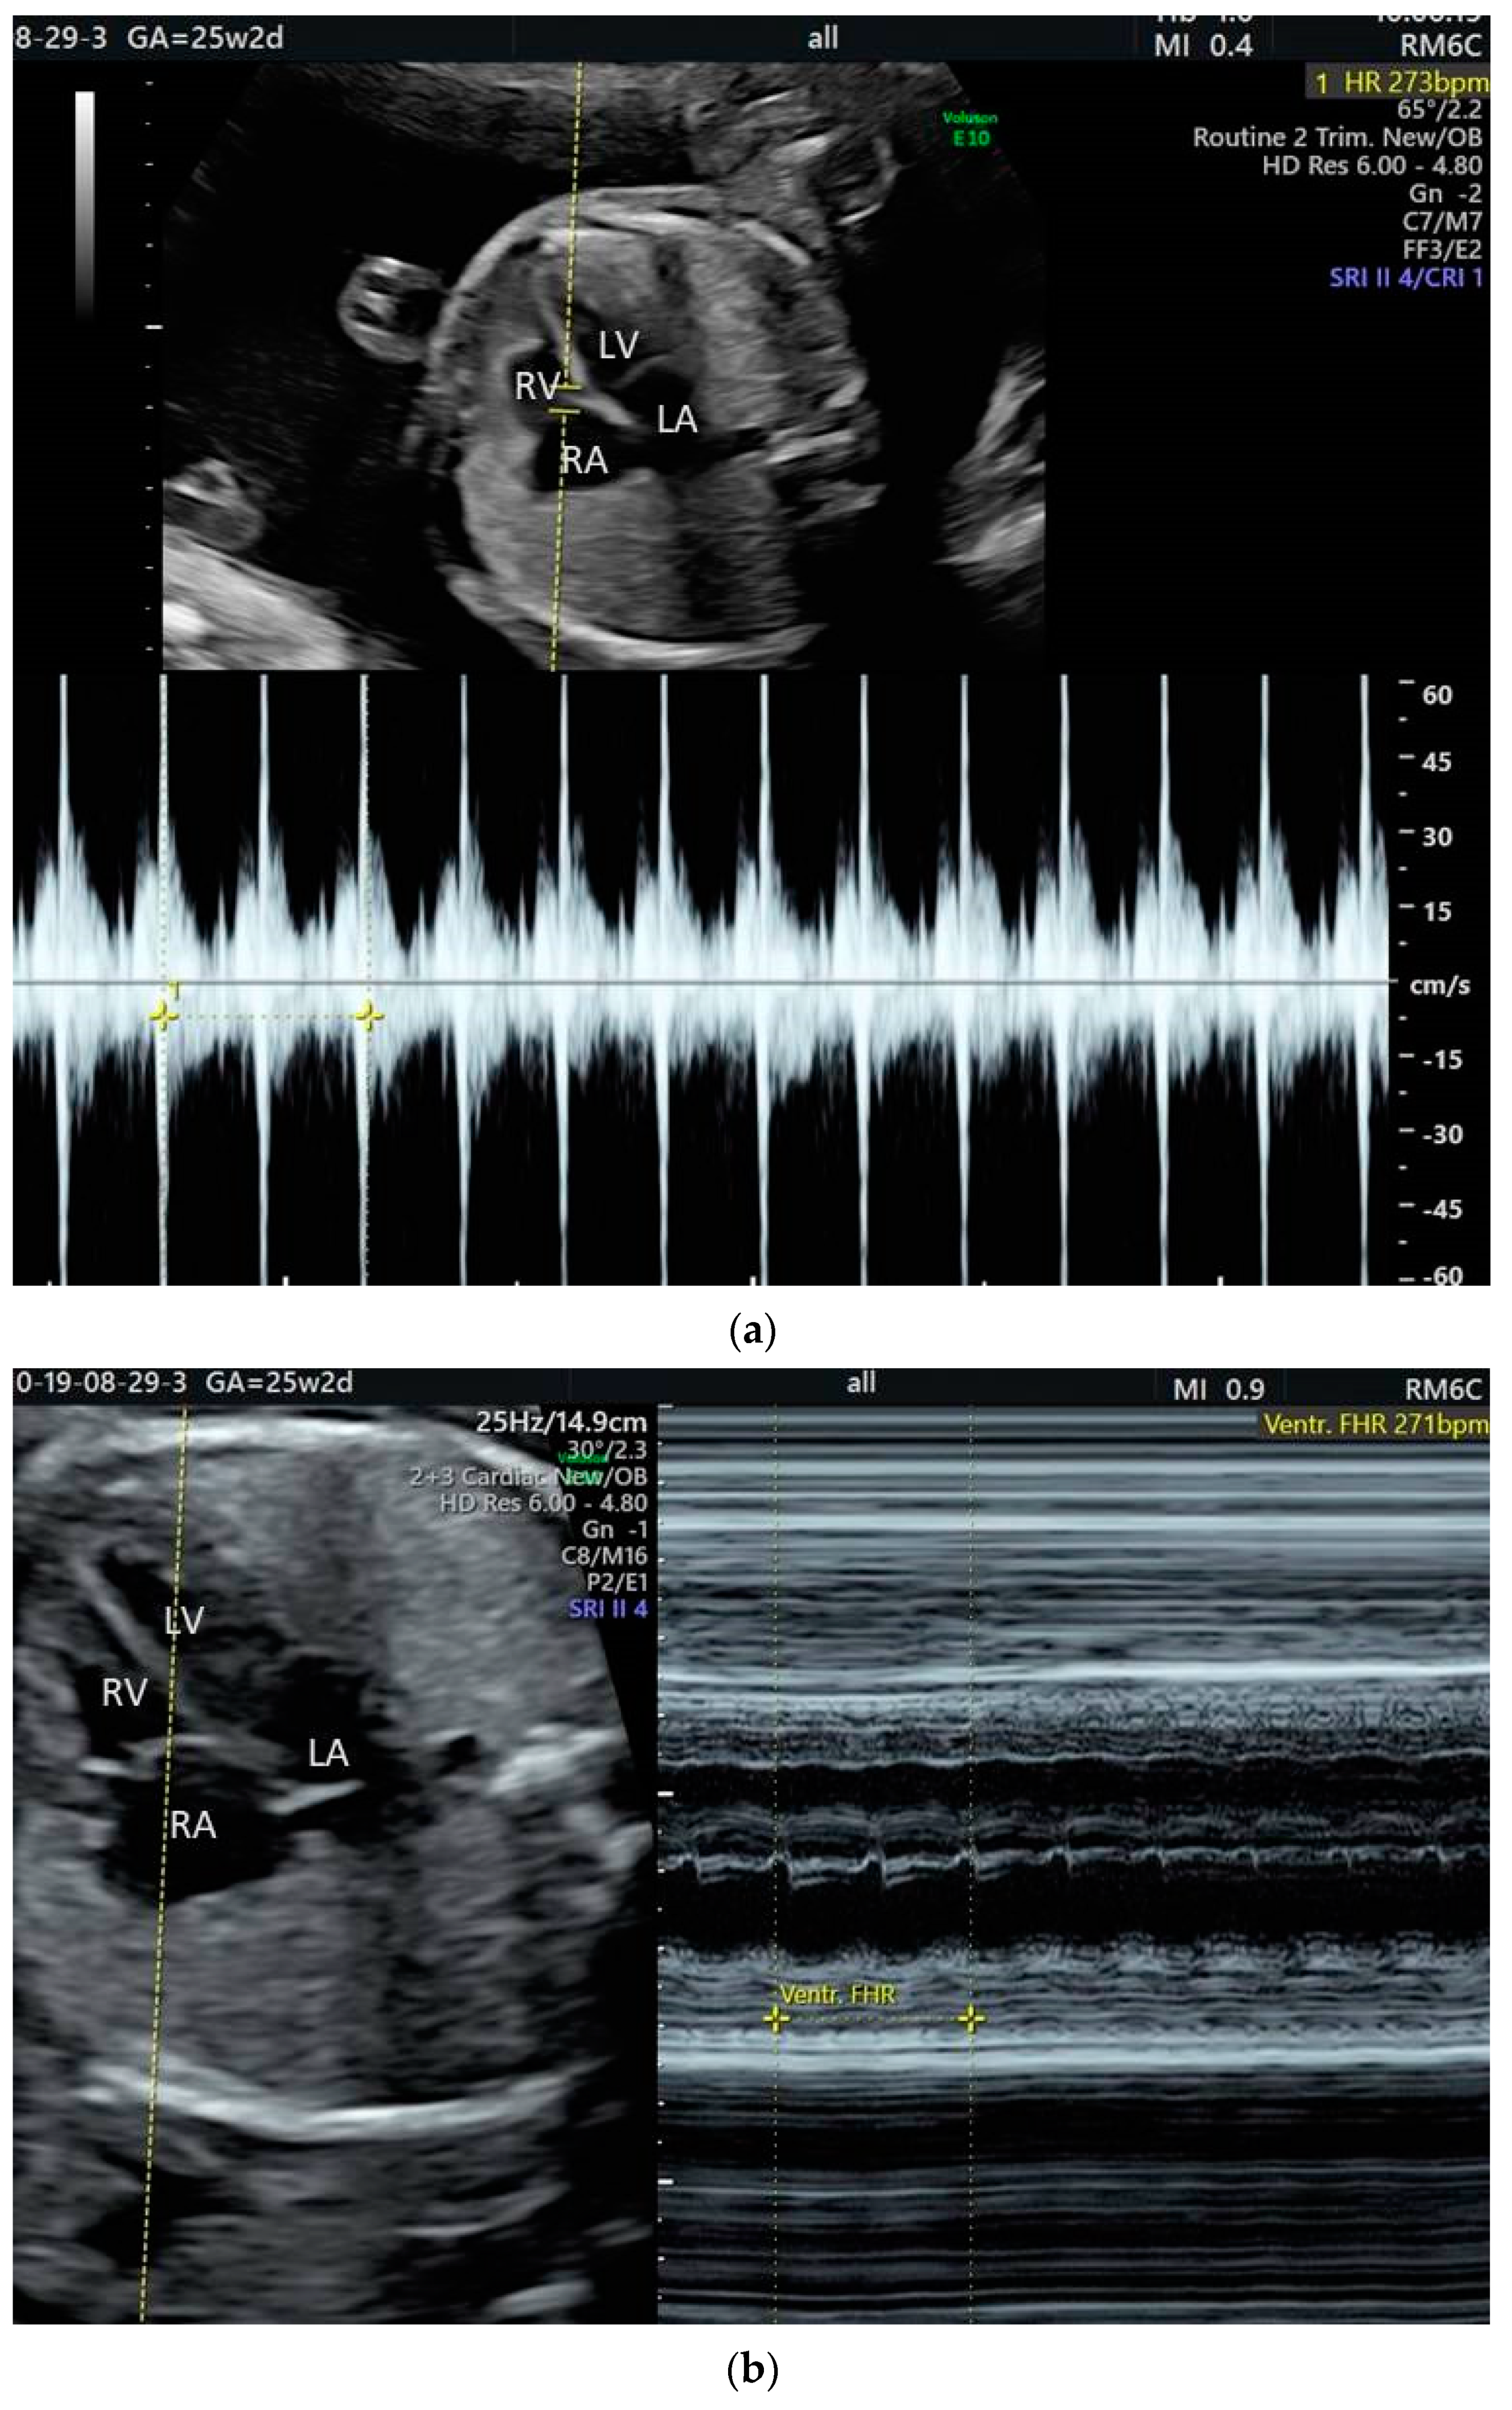

2. The Use of Ultrasound to Assess Fetal Heart Rhythm